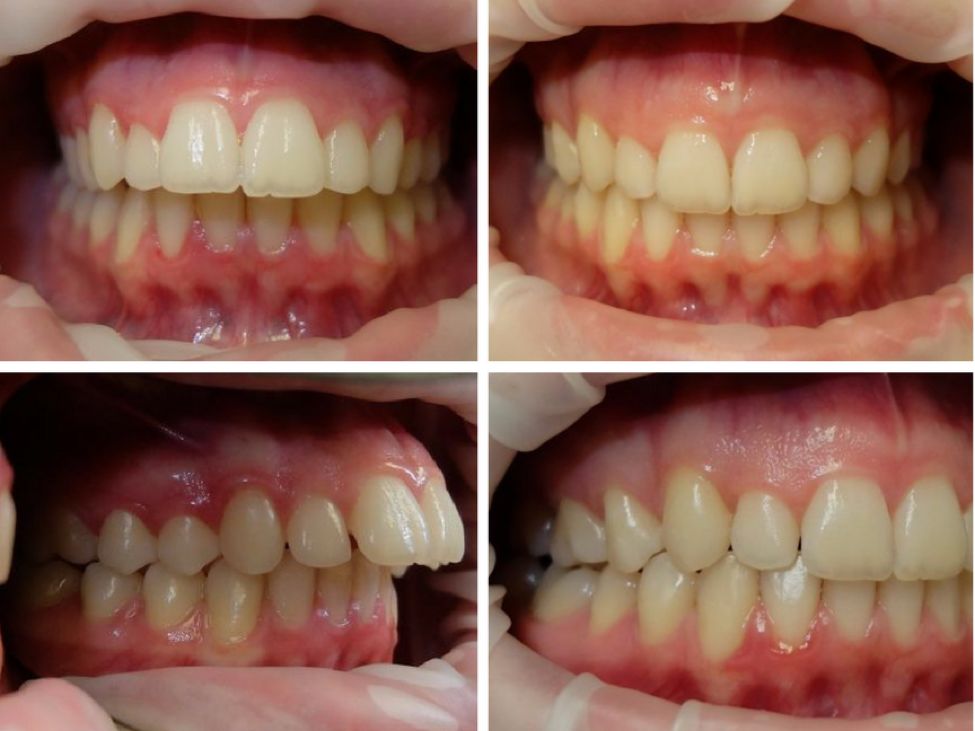

CASE 1

关键词

牙齿拥挤、虎牙突出、过咬合

这个牙挺乱的吧,虎牙突出,拥挤,深覆合,过咬合,这个是很多小伙伴都有的问题。看看看,这个case你们觉得够复杂吗?invisalign做到了,45个牙套,64周,16个月完成啦!

全头xray我们可以看到牙齿矫正前后侧面脸型和嘴型产生的变化。当然,由于她的过咬合非常严重(上下排差距太大),拔去了上牙的左右两颗第一前臼齿,能够把整个上排往后退并调整下排牙齿角度,使牙齿能够达到标准咬合。

45

16